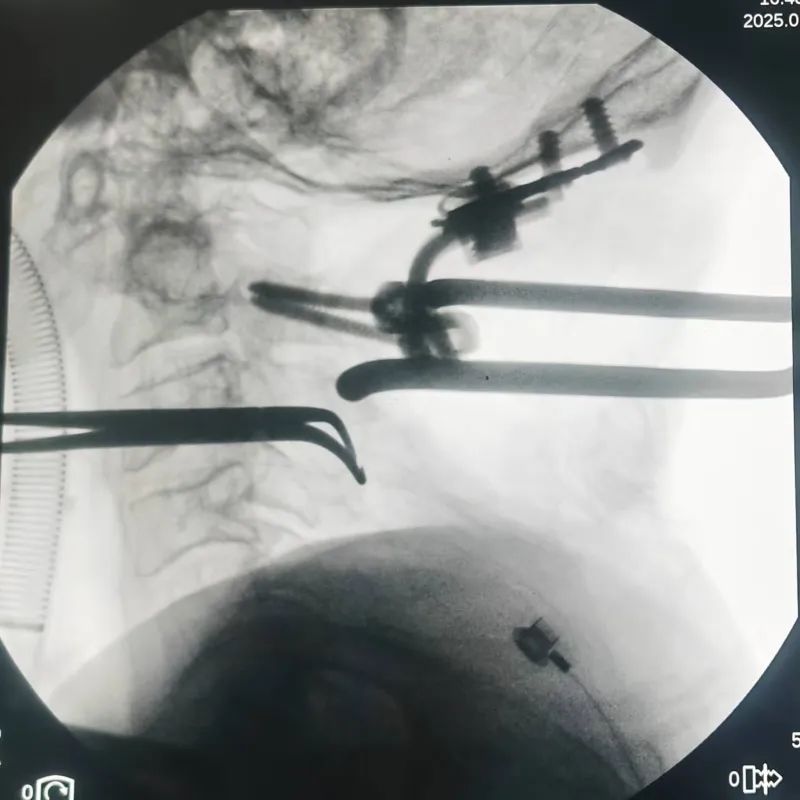

春节前夕,西安市第九医院神经外科成功收治了一名特殊患者。该患者此前被四肢麻木抽动困扰4年余,同时还伴有枕颈部疼痛及行走不稳的症状。一开始,以为是头部问题,于外院就诊后效果不佳,便来到西安市第九医院就诊。经诊断,确诊为:1.寰枢椎脱位 2.颈1-2椎体水平脊髓损伤。面对这一复杂病情,市九院

神经外科张西安、王振华团队迅速展开救治行动。鉴于患者寰枕交界处畸形,团队术前精心制作了枕颈交界区椎体及椎动脉3D打印模型。

术中医生们根据3D模型精准选择固定方式,并在显微镜下精细操作,不仅有效减少了出血,还成功避开椎动脉等重要颅内供血动脉,顺利完成椎体固定及融合。术后,患者寰枢椎复位情况理想,恢复良好,已顺利出院继续康复。

△术中复位寰枢关节